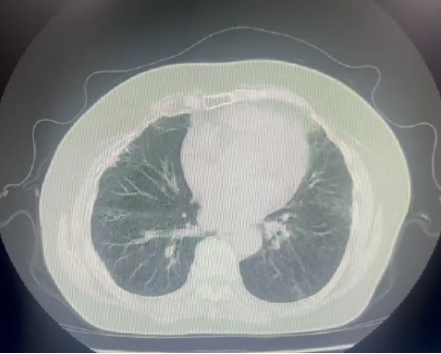

CT 影像:11 月 27 日复查胸部 CT,可见双肺磨玻璃渗出影明显吸收,对比 11 月 18 日影像,肺部病变改善显著。

11月27日肺部CT

患者肺部影像学提示双肺间质纤维化伴磨玻璃样渗出影,考虑慢性纤维化性间质性肺病伴急性感染,患者高龄、免疫低下,给予呼吸支持的同时积极抗细菌、抗机会性感染。入院时血气提示I型呼吸衰竭,结合影像表现符合急性呼吸窘迫综合征,在基础治疗的同时应积极对抗全身炎症反应,西维来司他钠作为核心抗炎抗纤维化药物,它的应用是本次治疗的关键。其独特机制可针对性抑制肺部炎症反应和纤维化进展,与尼达尼布存在协同作用。避免了长期大剂量激素带来的血糖升高、感染风险增加等不良反应,符合当前间质性肺病治疗中 “减少激素依赖” 的趋势。从治疗效果来看,患者炎症指标快速下降、肺部病变显著吸收,证实了该药物在慢性纤维化性间质性肺病急性加重中的重要作用,尤其适用于非感染性炎症主导的病情进展。但西维来司他钠与尼达尼布联合使用的协同机制尚需更深入的基础研究验证,是否可根据患者具体表型调整剂量或用药时长,以达到更优治疗效果仍需讨论。